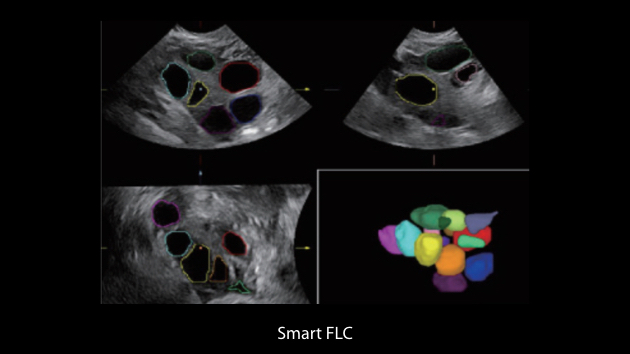

El sistema Nuewa I9, dise?ado exclusivamente para la atenciĂłn mĂ©dica neonatal y de mujeres, brinda una experiencia innovadora integral. Estas innovaciones se desarrollan sobre la base de un conocimiento profundo de situaciones clĂnicas complejas para proporcionar respuestas precisas y oportunas, una gran eficiencia y una experiencia de usuario extraordinaria.

La plataforma ZST+?es una innovaciĂłn extraordinaria que representa toda una evoluciĂłn en el ĂĄmbito de la ecografĂa. Transforma las mĂ©tricas ecogrĂĄficas de la formaciĂłn de haces convencional al procesamiento basado en datos de canal. Supera la limitaciĂłn tradicional de tener que equilibrar entre resoluciĂłn espacial, resoluciĂłn temporal y uniformidad del tejido, con lo que ofrece una calidad de imagen excepcional para soluciones de producciĂłn de imĂĄgenes infinitas con mejoras continuas.